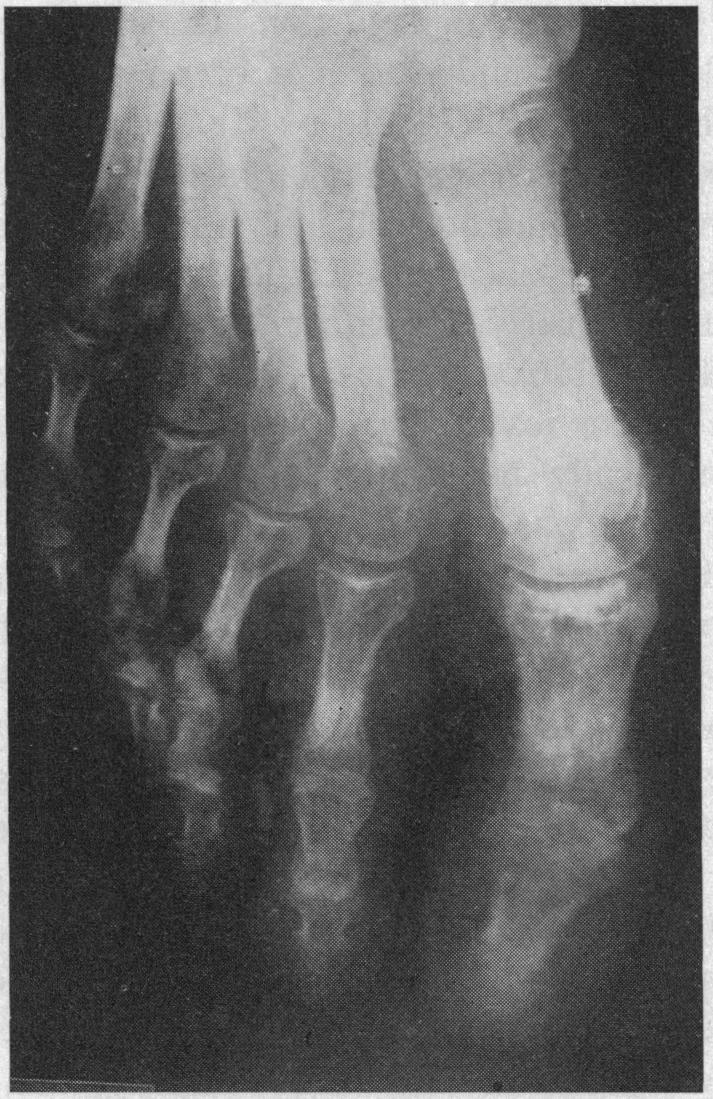

Reiter's syndrome.

Calif Med. 1966 Aug;105(2):129-36.